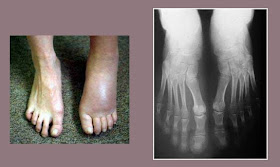

La déformation en varus (en dedans) du pied est liée au déplacement en dedans de la tubérosité du calcanéum au moment du traumatisme, tirée par le complexe musculaire du triceps sural du mollet par l’intermédiaire du tendon d’Achille. Elle est mal tolérée car déséquilibrant le pied et en induisant un transfert de charge sur le bord externe du médio et de l'avant-pied. Cliniquement les traumatisés décrivent des douleurs sur le bord externe du pied, au niveau de la base du cinquième métatarsien et occasionnellement ils peuvent présenter des ulcères de surcharge sur la base du cinquième métatarsien ainsi que des fractures de stress. Certains patients décrivent des entorses de cheville en varus et des tendinites des tendons péroniers à répétition. Une radiographie axiale et l’examen clinique des arrière-pieds (perte du valgus calcanéen physiologique) permettent de poser le diagnostic. L’examen clinique de dos est très démonstratif: en position bipodale on observe une translation du talon en dedans et une zone d’hyper-appui sur le bord externe du médio-tarse avec parfois une hyperkératose au niveau de la base du cinquième métatarsien et des tendons péroniers sensibles à la palpation.

Perte de hauteur de plusieurs centimètres de l’arrière-pied secondaire à la compression du calcanéum qui s'accompagne d'un dysfonctionnement des articulations voisines de la cheville et horizontalisation du long axe de la cheville

L'élargissement du calcanéum lié à la compression va entraîner un conflit avec la malléole externe de la cheville et des douleurs